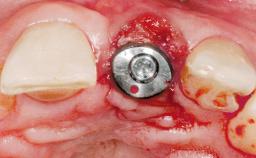

Late Placement of an Implant in a Maxillary Left Central Incisor Site

# of Implants 1

Type of Implants Two-Piece

Bone Augmentation Horizontal|Staged

SAC Level Complex

Placement Protocol Early or late implant placement